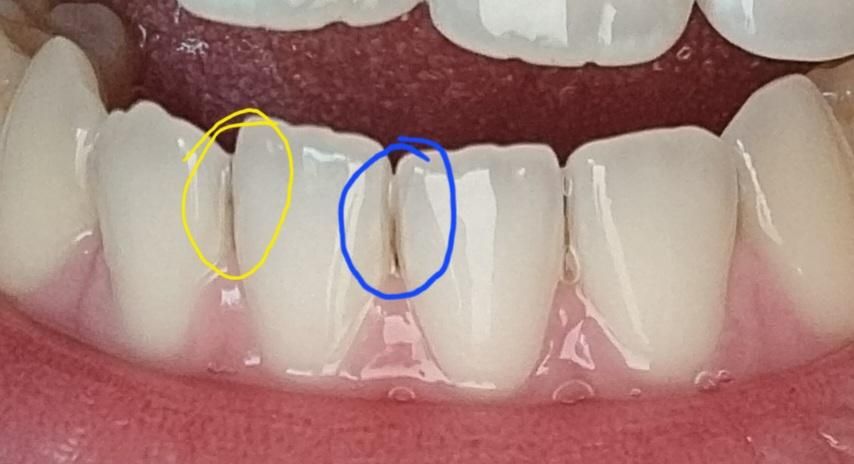

아랫니 사이 상태 착색?! 치석?!!

• 노란색 부분 - 약간 연한 점이 생겨있는데 착색일까요?

• 파란색 부분 - 최대한 빼보려고 양치해도 안 빠지고 치실도 안 들어가는데 치석인가요?

스케일링은 12월에 전체적으로 했고 6개월마다 정기점진 하고 있어요

1. 충치 가능성도 있고 착색 가능성도 있습니다

2. 치석같습니다 치석은 치태와 달리 치실로 제거 안됩니다 치과가서 부분적으로 다시 스케일링 받으세요 부분스케일링은 얼마 안합니다

사진 흐려 명확히 말씀드리기 어려운점 양해부탁드립니다. 사진상으로는 노란색부분 우식 의심할 만한 부분 없거나 있더라도 정지우식정도로 보이며 파란 부분은 설측 사진이 있어야 명확히 알 수 있으리라 보입니다. 순측사진에서는 명확히 보이는 부분은 없어보입니다.